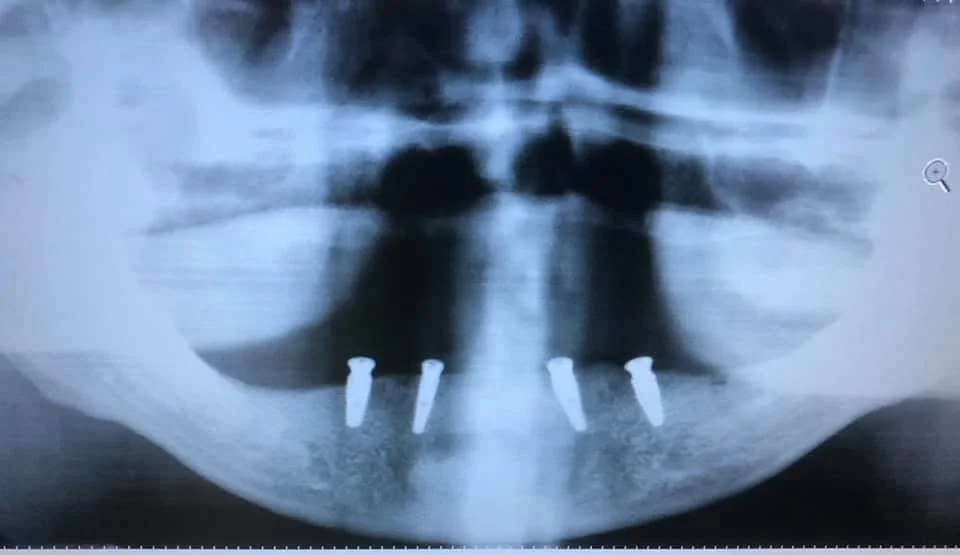

Dental Implants

Unlike dentures or bridges, dental implants are surgically placed in the jawbone, offering superior stability and long-term results. Each implant is topped with a custom crown that looks and feels just like a natural tooth, allowing you to eat, speak, and smile with confidence. Whether you’re missing one tooth or several, we’ll guide you through the process with clarity, compassion, and advanced surgical techniques.

Before & After

See how dental implants can transform more than just your smile, with natural-looking results that restore confidence, comfort, and long-term function.